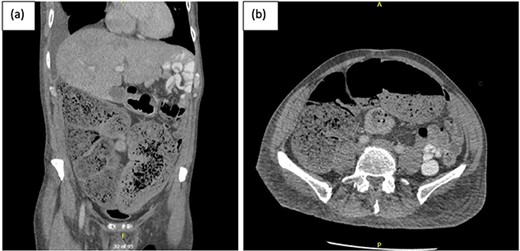

A week later, the patient reported new central abdominal pain with associated nausea and his last bowel action was almost 1 week prior. On examination, his abdomen was distended with generalized tenderness, but there was no peritonism. He was subsequently treated with regular oral laxatives, but with no improvement. A computed tomography (CT) abdomen and pelvis with oral and intravenous contrast was performed, which demonstrated marked faecal loading in the ascending and transverse colon with no convincing evidence of mechanical bowel obstruction (Fig. 1).

(a) Coronal and (b) axial views of CT abdominal pelvis, with oral and intravenous contrast demonstrating significant faecal loading in ascending colon and proximal to mid-transverse colon.